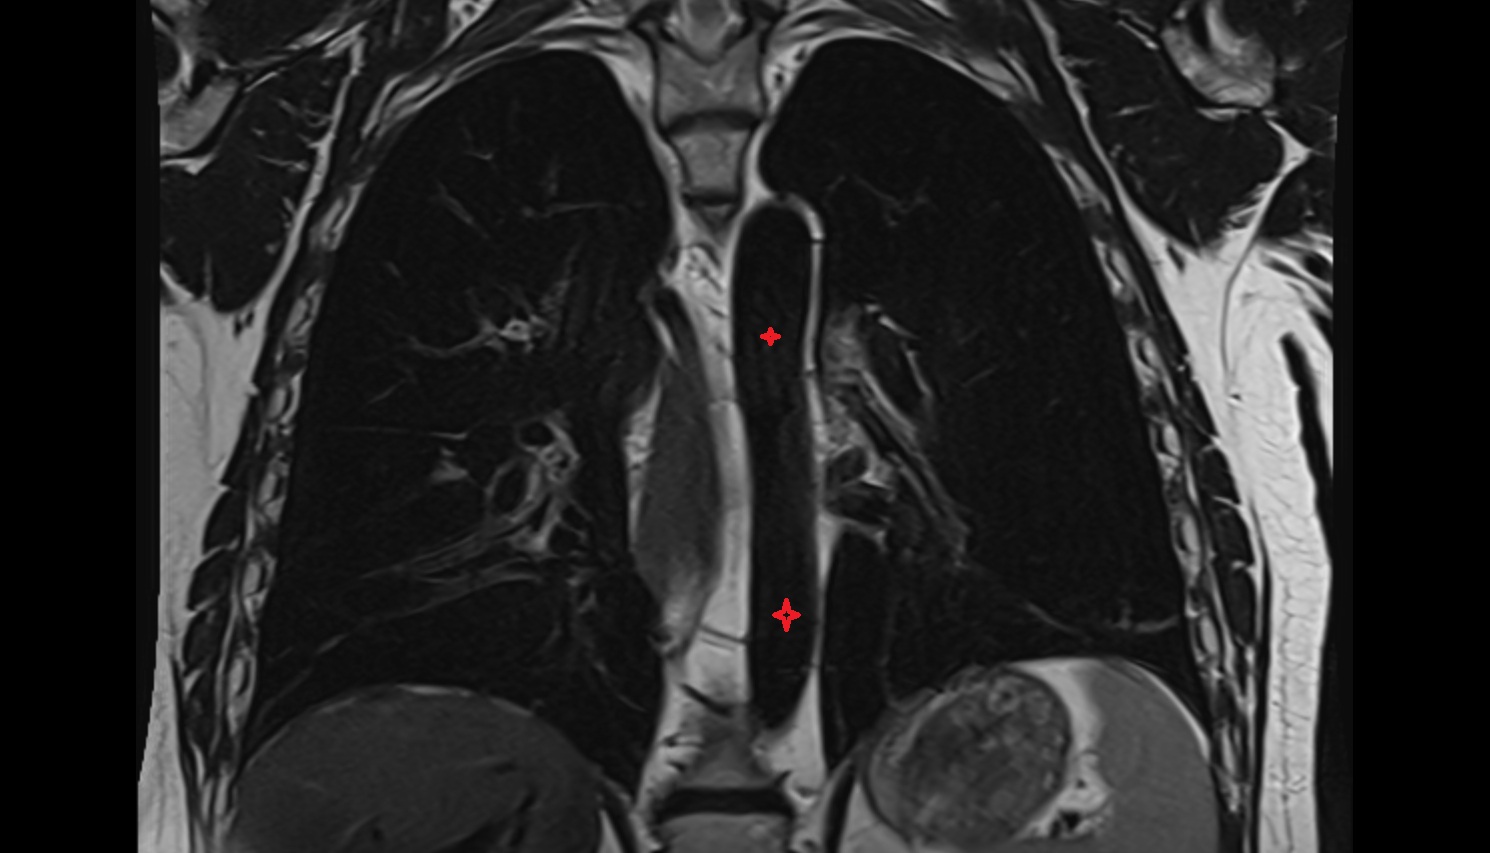

- Thoracic part of esophagus

- Descending thoracic aorta

- Esophagus